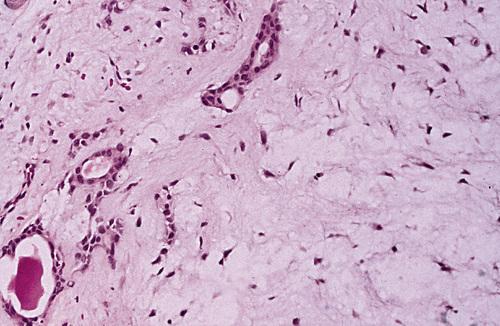

Chronic inflammatory infiltrate with associated acinar atrophy, ductal dilatation, and fibrosis.

chronic sclerosing sialadenitis